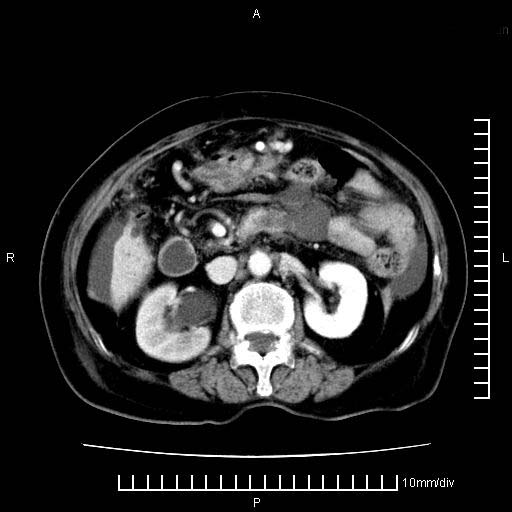

标题: CT28280:腹部增强:女性,80岁

上腹疼痛月余,外院核磁诊断胰腺癌。现临床示右下腹可明显触及包块,可片子上怎么没有看到?

胰腺体部癌累及周围器官,腹膜、粘连

胰腺体部癌累及周围器官,腹膜、粘连,临床摸到的可能是粘的组织

胰腺结构模糊,胰尾部见囊性包块,周围脂肪密度增高,左肾前筋膜增厚,胸水、腹水。不符合胰腺ca伴腹膜腔转移。考虑胰腺炎伴假性囊肿形成、胸腹腔积液。

右肾盂囊肿。

1)考虑胰腺癌并胰腺假性囊肿形成。2)肝内低密度灶,不排除转移。3)右肾盂积水。4)腹水。5)右侧胸腔积液并右肺下叶部分膨胀不全。

考虑胰腺ca伴腹膜腔转移、肝左叶转移、右肾积水。右胸腔积液。